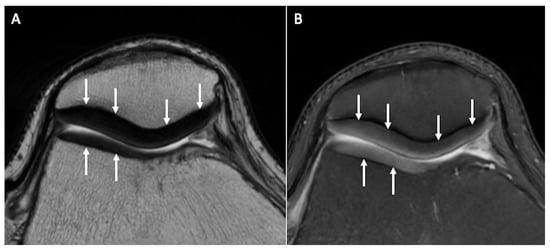

2.2. Cartilage Morphometry

- Graichen, H.; Eisenhart-Rothe, R.V.; Vogl, T.; Englmeier, K.; Eckstein, F. Quantitative assessment of cartilage status in osteoarthritis by quantitative magnetic resonance imaging: Technical validation for use in analysis of cartilage volume and further morphologic parameters. Arthritis Rheum. 2004, 50, 811–816. [Google Scholar] [CrossRef] [PubMed]

- Eckstein, F.; Cicuttini, F.; Raynauld, J.-P.; Waterton, J.; Peterfy, C. Magnetic resonance imaging (MRI) of articular cartilage in knee osteoarthritis (OA): Morphological assessment. Osteoarthr. Cartil. 2006, 14 (Suppl. S1), 46–75. [Google Scholar] [CrossRef] [PubMed]